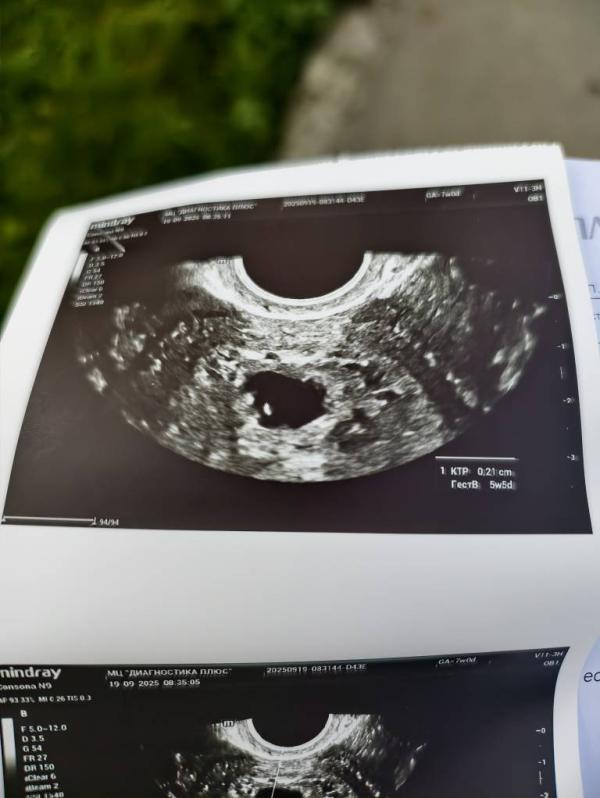

Ну какая она крошка 🥹🫰🏼 2,3 мм, матка подросла, плодное яйцо тоже, желточный мешочек на месте, красивый такой

Акушерских 7, НО первый день месячных 1 августа, овуляция 17-19 августа(цикл 31-33 дня), ик было 28 августа, тени на тестах 29 августа. Врач сказала всё в норме!

Сердечко Буси стучит!

@nat69876 не то слово, вообще) я что то так распереживалась, на этом сроке с сыном ктр был 7,3 мм... А тут на 5 мм меньше 🫣

У нас с Вами срок 1 в 1. О была 18 августа, вчера на узи намерили 4,8 мм ктр, сегодня у врача спросила об этом. С ее слов, на этом сроке самые большие погрешности на узи. Стоит малышу повернуться под определенным углом, тут же аппарат срезает несколько мм. Поэтому нужно идти теперь в 8-9 недель, будет более информативно